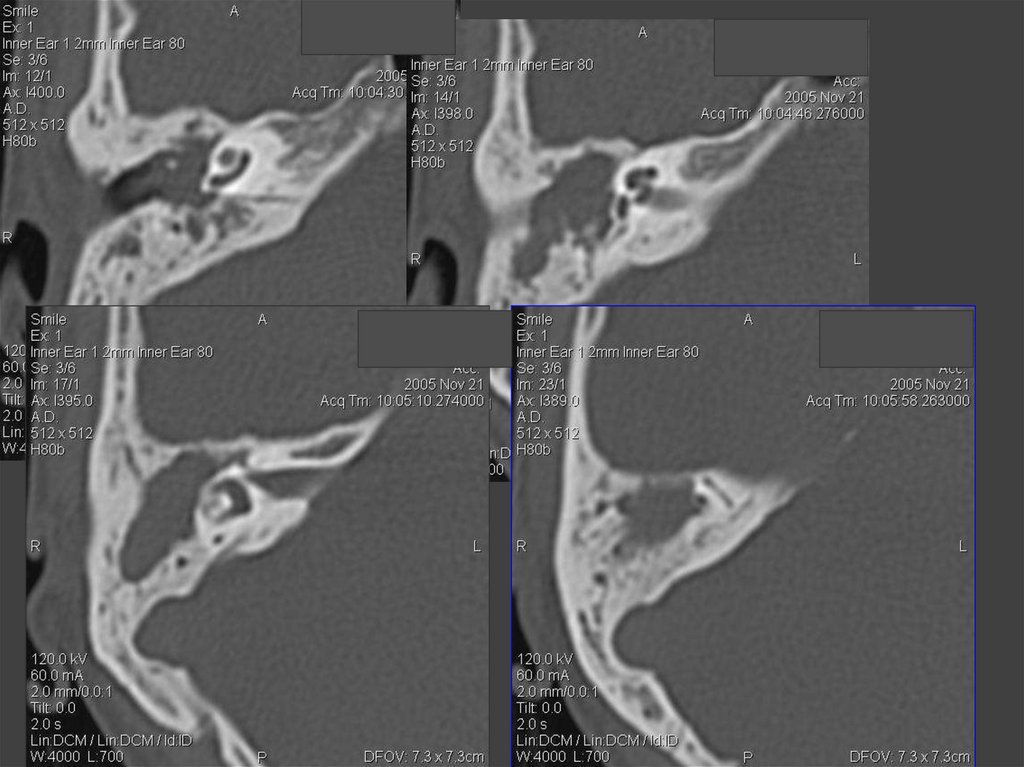

81. Внутриканальная акустическая невринома (по Swartz J.D. and Harnsberger H.R. 1998)

82. Акустическая невринома

83. Акустическая невринома

НЕВРИНОМА СЛУХОВОГО НЕРВА

КТ — признаками опухоли слухового нерва являются:

расширение слухового прохода, наличие округлого, реже

овального объемного образования, зачастую с очагами

кистозной дегенерации и хорошей реакцией на усиление,

острый угол между поверхностью опухоли и задней

поверхностью височной кости

ВСП шире 8 мм,

асимметрия >2 мм

подозрительны